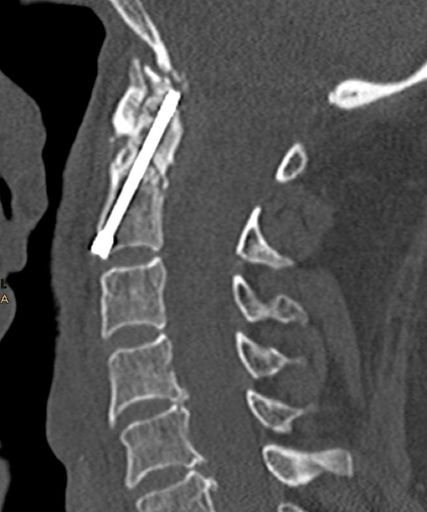

Abb. 1: Postoperative CT-Kontrolle nach Densverschraubung bei Densfraktur Typ IIb

Das chirurgische Management zielt darauf ab, das Risiko einer mobilen Pseudarthrose mit atlantoaxialer Instabilität bzw. sekundärer Dislokation und Fehlstellung zu minimieren sowie eine Besserung der Lebensqualität und Linderung der körperlichen Beschwerden zu erreichen. Eine Studie von Leister et al. ergab, dass eine posteriore Stabilisierung im Vergleich zur konservativen Therapie das Risiko einer Pseudarthrose signifikant verringert, während bei Patienten mit anteriorer Densverschraubung kein Unterschied festgestellt wurde.9